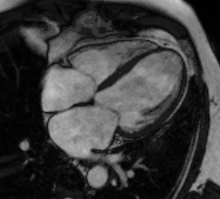

نقص دیواره بین دهلیزی با اتساع بطن راست توسط CMR